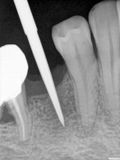

fredlibc | all galleries >> Galleries >> JLin - 45 implant > R1.jpg

R1.jpg